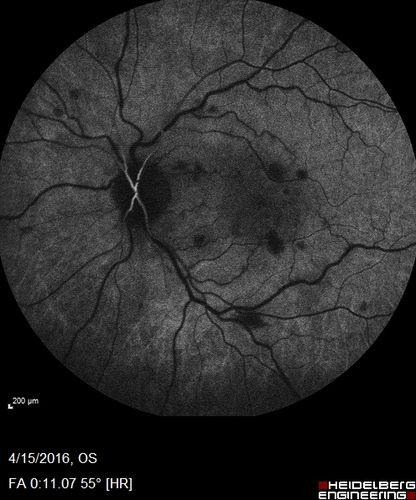

Central retinal artery and vein occlusion - Protein C Deficiency 33 year old male

33 year old male with vision loss for 3 hours.  VA 20/12 right eye, 5/200 left eye.  He has a protein C deficiency.  The left eye recovered vision in about 1 month to 20/16.  FA shows very slow recirculation time.